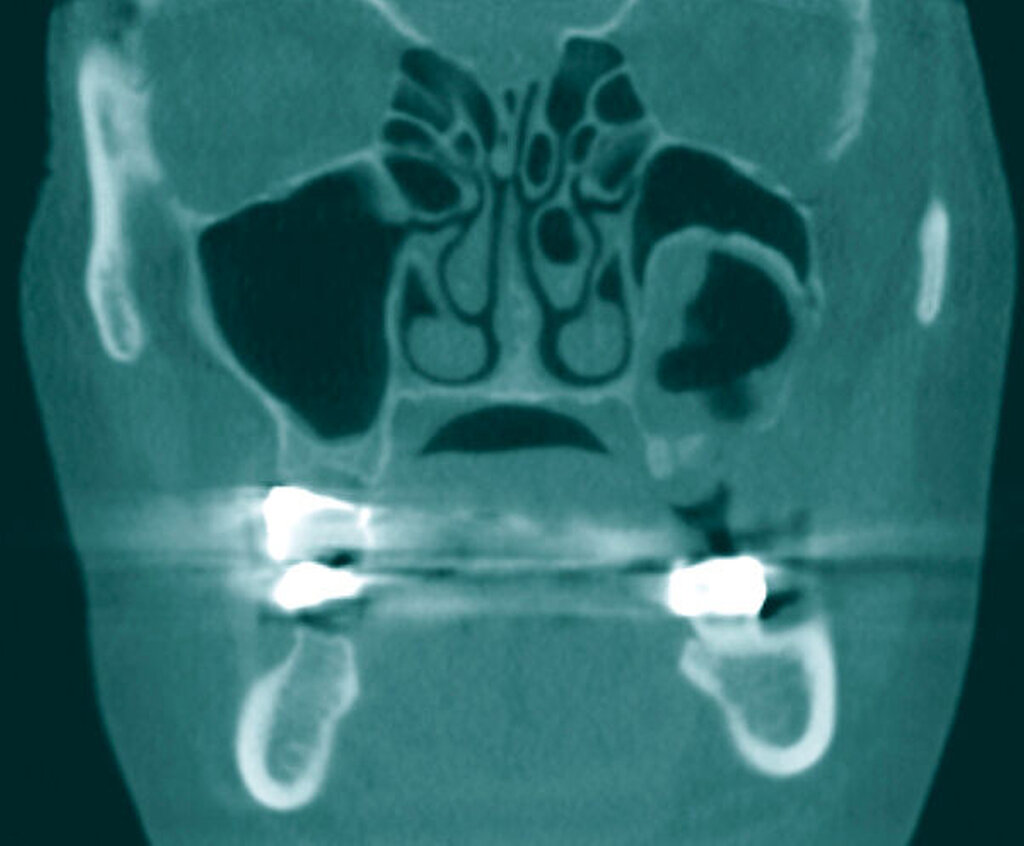

Die präoperativ durchgeführte Digitale Volumentomografie (DVT) zeigte eine zystische Raumforderung, die fast zwei Drittel der linken Kieferhöhle einnahm. Die Raumforderung hatte randständig eine weichgewebedichte Opazität mit zentraler Transluzenz und erschien fast „seifenblasenartig“. In regio 26/27 zeigte sich die bereits klinisch auffällige MAV. Radiologisch befand sich der Zahn 25 in direkter Nähe zum Befund. Das restliche Gebiss wies neben konservierenden und prothetischen Maßnahmen keine weiteren Auffälligkeiten auf (Abbildung 1).

Es wurde die Indikation zur Entfernung der Raumforderung samt Extraktion des Zahnes 25 gestellt. Nach crestal palatinaler Inzision und Umschneidung der MAV konnte ein mukoperiostaler Lappen gebildet und die faziale Kieferhöhlenwand großflächig dargestellt werden. Der Zahn konnte komplikationslos entfernt werden. Zur Einhaltung eines ausreichenden Sicherheitsabstands erfolgte die großflächige Osteotomie des linken Oberkiefers mit der Knochensäge bis zur anterioren Kieferhöhlenwand parallel zur Okklusionsebene (Abbildung 2). Distal erfolgte das Absetzen mit dem Obwegeser-Meißel. Der Befund konnte anschließend in toto entfernt werden (Abbildung 3) und die MAV mittels einer plastischen Deckung nach Rehrmann unter Verwendung des Bichat‘schen-Fettpfropfs mehrschichtig verschlossen werden.